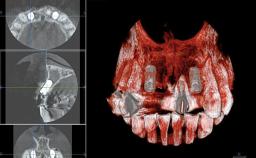

This 20-year-old woman was referred to our department in July 2006. Four months earlier, she had experienced dental trauma to the anterior maxilla when traveling in South America. The emergency treatment included emergency root canal treatment of teeth 12 and 11. Tooth 21 was also subjected to endodontic treatment later. At the initial examination, the patient was not in pain but reported increased mobility of tooth 12. The clinical examination revealed a high smile line, medium thickness of the soft tissue, and rectangular tooth forms. Discoloration of tooth 12 was evident. The periapical radiograph provided by the referring dentist indicated a fracture line at both teeth 12 and 11. A cone-beam computed tomography (CBCT) scan confirmed these fractures. No pathology was found to be associated with tooth 21.

Bone Volume Deficient horizontally, allowing simultaneous augumentation